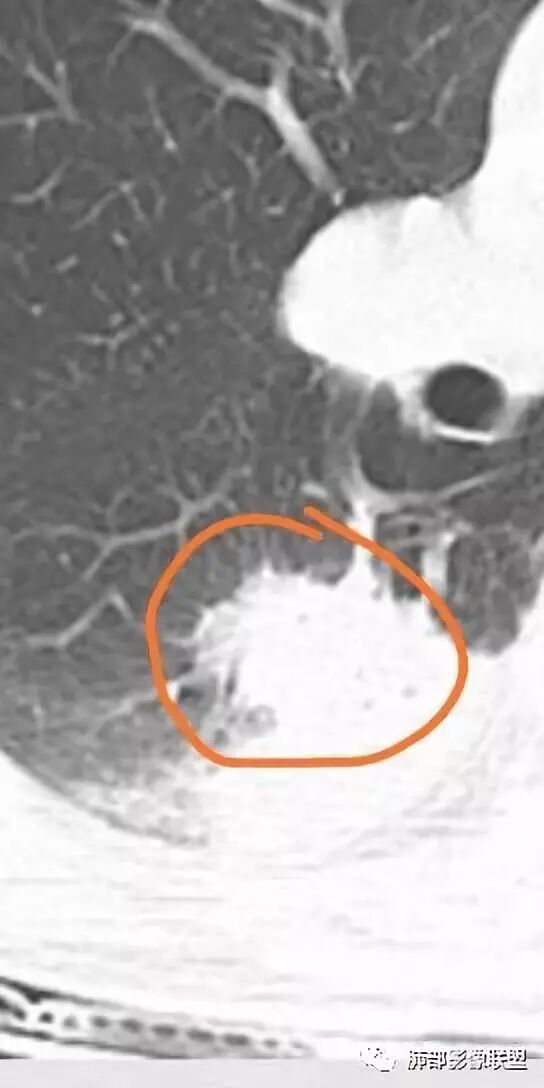

胸部CT:右肺下叶背段实变,广基底,糊墙,长轴与胸膜平行,周围晕,支气管进入堵塞,纵隔窗可见低密度坏死,实变内小空洞?脑部不会看。

胸CT:右肺下叶背段实变影,内可见小空泡,病灶与胸膜呈宽基底,实变病灶周围存在毛玻璃影,纵隔窗可见病灶内存在低密度,增强可见病灶强化,并见病灶内低密度区。头MRI不会看。

右肺下叶背段实变,广基底,糊墙,长轴与平行胸膜,周围有晕,支气管进入堵塞,可见低密度坏死及小空泡。颅内多发环形强化灶,符合脑脓肿三层结构,结合临床,考虑:感染性病变,隐球菌?鉴别肺克。

蔡磊:

肺部病灶有收缩性,支持感染性病变,但是患者病程不急,不支持肺克

右肺下叶大片实变

我们回头看肺内的,病灶位于下叶背段,可惜没重建

近肺门区见一坏死腔,内壁较清楚,空泡在周围

单从这个坏死我们分析:1、炎性?2、鳞癌?

厚薄均匀,强化一致,未见壁结节,坏死位于病灶近端,我会首先考虑炎性

局部部分边缘膨隆,欠光滑

不是单纯的近端堵塞,远端不张,远端实变,宽基底

远端实变区膨隆,部分似有栽赃的趋势

感染一定有,但是应该还有警惕癌

南边:

一般来说炎性空洞坏死,空洞偏内的结核多,癌性空洞一般是远端的缺血坏死,这个病例特殊,近端支气管显示不清,内壁部分清晰,部分不清晰,是不是层厚的问题?

炎性有。从总体来说,病变分两部分,靠肺门这里是一个弧形的。从影像来说,确实有些壁不是很清楚,层厚、窗宽窗位影响,这个壁细节显示不是那么清楚。大点病灶是一个有分叶的,宽基底在外侧,病灶边缘有膨隆的迹象。

少量积液反衬外壁更好看,靠近胸膜侧有很多积液不连续,断掉,局部膨隆在外面。很大一部分是连续的,但有些部分是不连续的。有膨隆我就很难判断,病灶的膨隆是张力引起的,还是远端栽赃引起的?局部的胸膜有变化的。所以我怀疑有栽赃的趋势,为什么说趋势,是因为没看到外面一个侵犯的迹象,但是层厚原因我有些地方我不敢说,有没有侵犯。

你看我标的这个地方,我就觉得这个病灶有侵犯性,附近旁边都有一个低密度线影,局部就没了,病灶似乎直接到个肋骨的胸膜脂肪间隙下,这些地方都有类似迹象,把它当成一个大的肿块,有分叶,近端有坏死、空洞,壁外围还有有些毛糙,腔内也有些索条影。颅脑内像个转移瘤的特点,转移瘤,淋巴瘤,脓肿?脓肿腔内脓液粘稠,弥散受限,这个腔内DWI不高,这个让我犹豫.按理脓肿也要考虑.

2.影像右肺下叶大片高密度影,整体边界模糊柔和,中央见圆形液化区及微小气泡影,内壁相当光整,环形强化,未见明确壁结节。双肺门及纵隔未见增大淋巴结。这样的病灶更符合细菌性肺脓肿,以肺炎克雷伯杆菌感染最为常见。